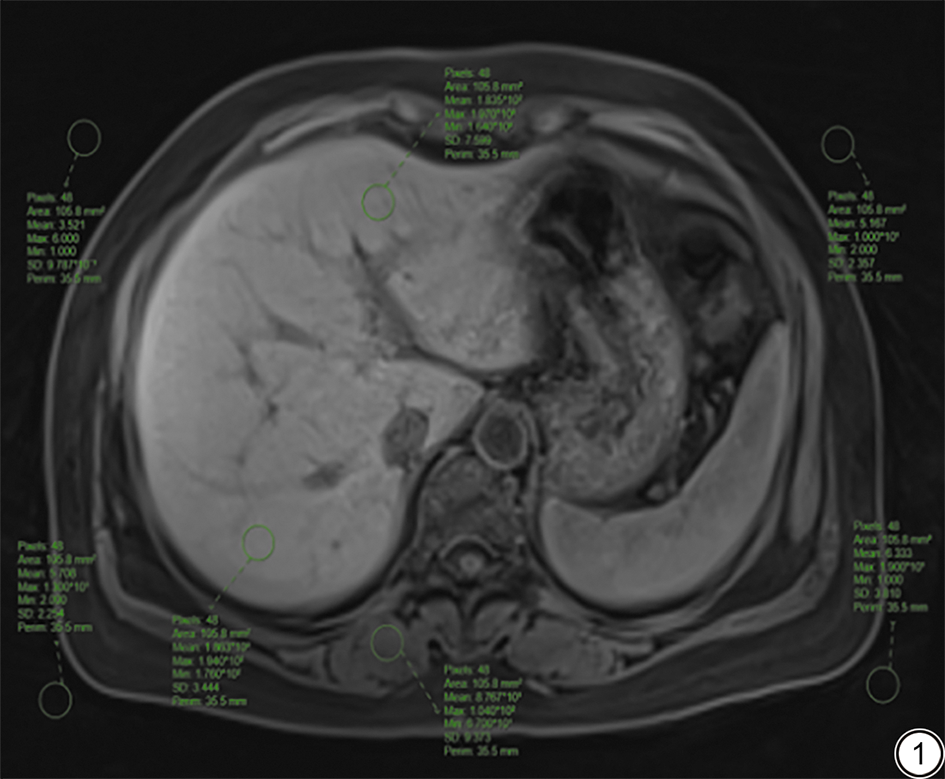

由2位分别具有10年(副主任医师)和5年(主治医师)腹部诊断工作经验的放射科医师在不知晓患者分组信息情况下,在所有患者CS-GRASP序列动态对比增强平扫、动脉早期和动脉晚期图像上,分别选取肝门静脉主干、左支及右支3个层面进行测量,在每个层面的肝左、右叶轴位中心区域、竖脊肌及图像四角各放置1个感兴趣区(region of interest, ROI)(图1),记录其信号值(signal intensity, SI)、标准差(standard deviation, SD)及图像背景噪声标准差的平均值(SD噪声),ROI放置避开较大的胆管、血管,面积约为105 mm2。分别计算肝左、右叶SI变异系数(coefficient of variation, CV),信噪比(signal-to-noise ratio , SNR),以及对比噪声比(contrast-noise-ratio, CNR)。具体公式如下:

图1  ROI勾画示意图。男,61岁,CS-GRASP序列优化组肝脏平扫图像,选取门静脉左支层面测量肝右叶轴位中心区域、肝左叶轴位中心区域、竖脊肌的信号值、标准差以及图像背景噪声标准差值。ROI:感兴趣区;CS-GRASP:压缩感知黄金角径向稀疏并行采样。

Fig. 1  Schematic diagram of ROI delineation. A 61-year-old male patient with optimized CS-GRASP liver images, selecting the left portal vein slice to measure the signal values, standard deviations of the right liver lobe central region in axial view, left liver lobe central region in axial view, and erector spinae, and the background noise standard deviation value. ROI: region of interest; CS-GRASP: compressed sensing golden-angle radial sparse parallel.